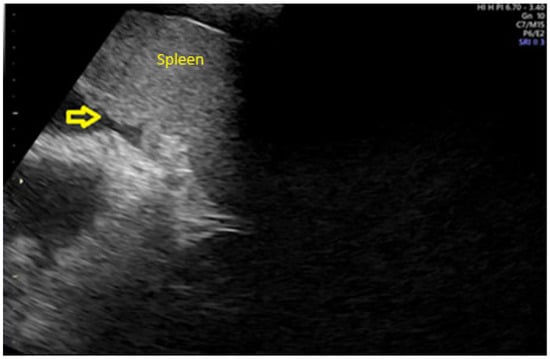

- Fischerova, D.; Zikan, M.; Semeradova, I.; Slama, J.; Kocian, R.; Dundr, P.; Nemejcova, K.; Burgetova, A.; Dusek, L.; Cibula, D. Ultrasound in preoperative assessment of pelvic and abdominal spread in patients with ovarian cancer: A prospective study. Ultrasound Obstet. Gynecol. 2017, 49, 263–274. [Google Scholar] [CrossRef]

- Tomasinska, A.; Stukan, M.; Badocha, M.; Myszewska, A. Accuracy of Pretreatment Ultrasonography Assessment of Intra-Abdominal Spread in Epithelial Ovarian Cancer: A Prospective Study. Diagnostics 2021, 11, 1600. [Google Scholar] [CrossRef]

- Alcázar, J.L.; Caparrós, M.; Arraiza, M.; Mínguez, J.A.; Guerriero, S.; Chiva, L.; Jurado, M. Pre-operative assessment of intraabdominal disease spread in epithelial ovarian cancer: A comparative study between ultrasound and computed tomography. Int. J. Gynecol. Cancer 2019, 29, 227–233. [Google Scholar] [CrossRef]